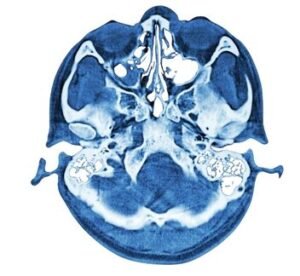

How Endoscopic Skull Base Surgery Works

Surgery is performed through the nasal passages, avoiding external scars.

A thin endoscope provides a clear, magnified view of the surgical site.

Specialized instruments are used to carefully dissect and remove the tumor.

Intraoperative MRI or CT scans may be used for navigation and confirmation of complete tumor removal.

This approach reduces trauma, shortens hospital stay, and speeds up recovery.